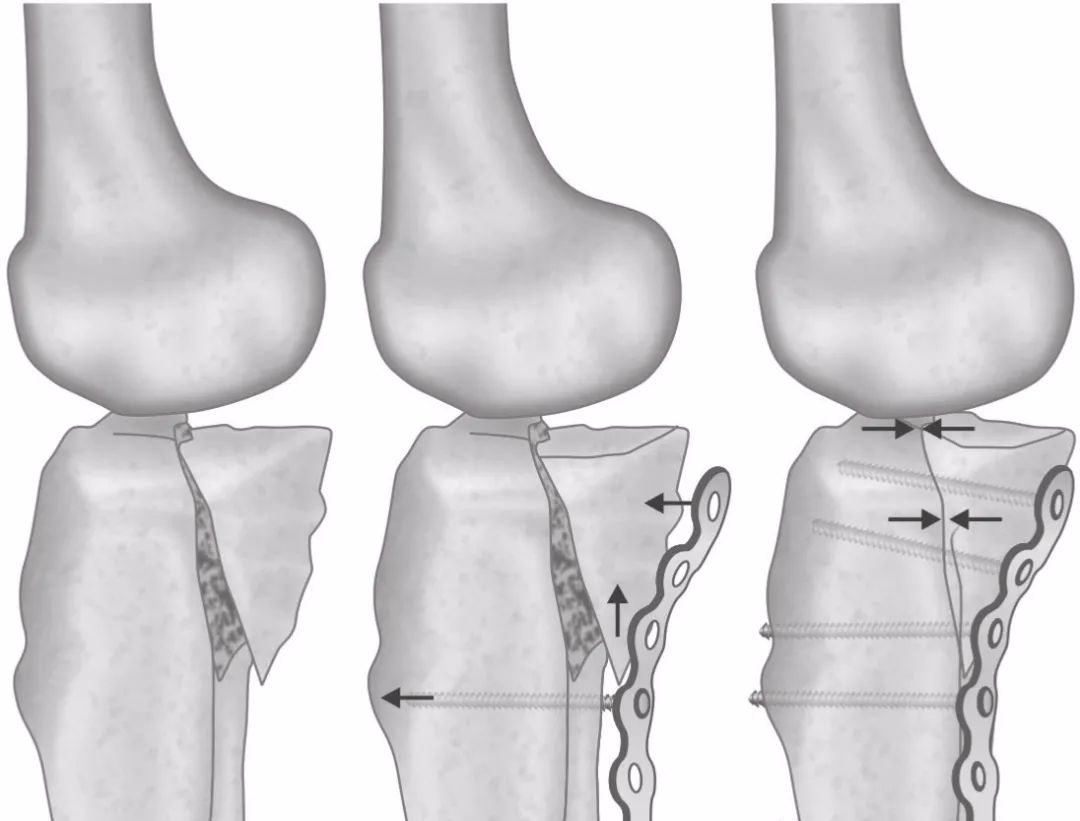

图15 A和B后内侧剪切骨折中使用防滑钢板的原则。(A)典型的移位是向下和向后内侧移位。(B)经塑形的3.5重建钢板用于支撑骨折块。第1枚螺钉植入骨折线远端2~3mm的胫骨干上。拧紧螺钉将造成骨折块向前外侧和上方移动。最终达到复位。(C)在透视下,置入近端螺钉,以增加折端的压力,从而提高塑形钢板的支撑效果